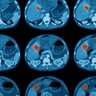

Celiac plexus ablation⚡️! Never seen one? Check out how it's done and maybe suggest it next time for your pancreas patient with intractable pain! econtour.org/cases/172 And you know it's good cuz @NiuSanford reviewed the case! Thanks Peter Lee, MD @FoxChaseCancer for the case

eContourRadOnc's tweet image. Celiac plexus ablation⚡️!

Never seen one? Check out how it's done and maybe suggest it next time for your pancreas patient with intractable pain!

econtour.org/cases/172

And you know it's good cuz @NiuSanford reviewed the case! Thanks Peter Lee, MD @FoxChaseCancer for the case